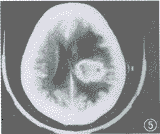

图4 9个月后头颅CT复查显示病灶增大,边缘小囊状影增多、增大。周围脑组织水肿加重

图5 图4增强扫描,病灶周边环状强化,小囊状影无强化